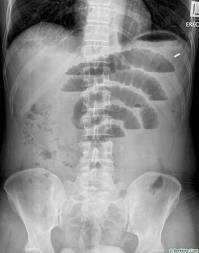

- Aspect radiologique ASP

de occlusion de l'intestin aigue : Dilatation de l'intestin en amont

de l'ostacle . Images

hydro-aeriques au centre de l'abdomen et situe en escalier et

sa largeur est plus de sa hauteur . Perdre de image aerique

en aval de l'ostacle . Les plies muqueuse de l'intestin est

multiple et en image de chapelet . Aspect radiologique de

paralyse de l'intestin c'est image de dilatation etendue de

l'intestin grele et de la colon .

| Aspect radiologique ASP

de occlusion intestinal : Image hydro-arerique

des anses de l' intestin dilate et isolee au milieu de

l'abdomen . Les plies muqueuse de l'intestin sont

multiple et image de vide en aval de l'obstacle (

n'as pas image de air dans la region pelvienne ) |